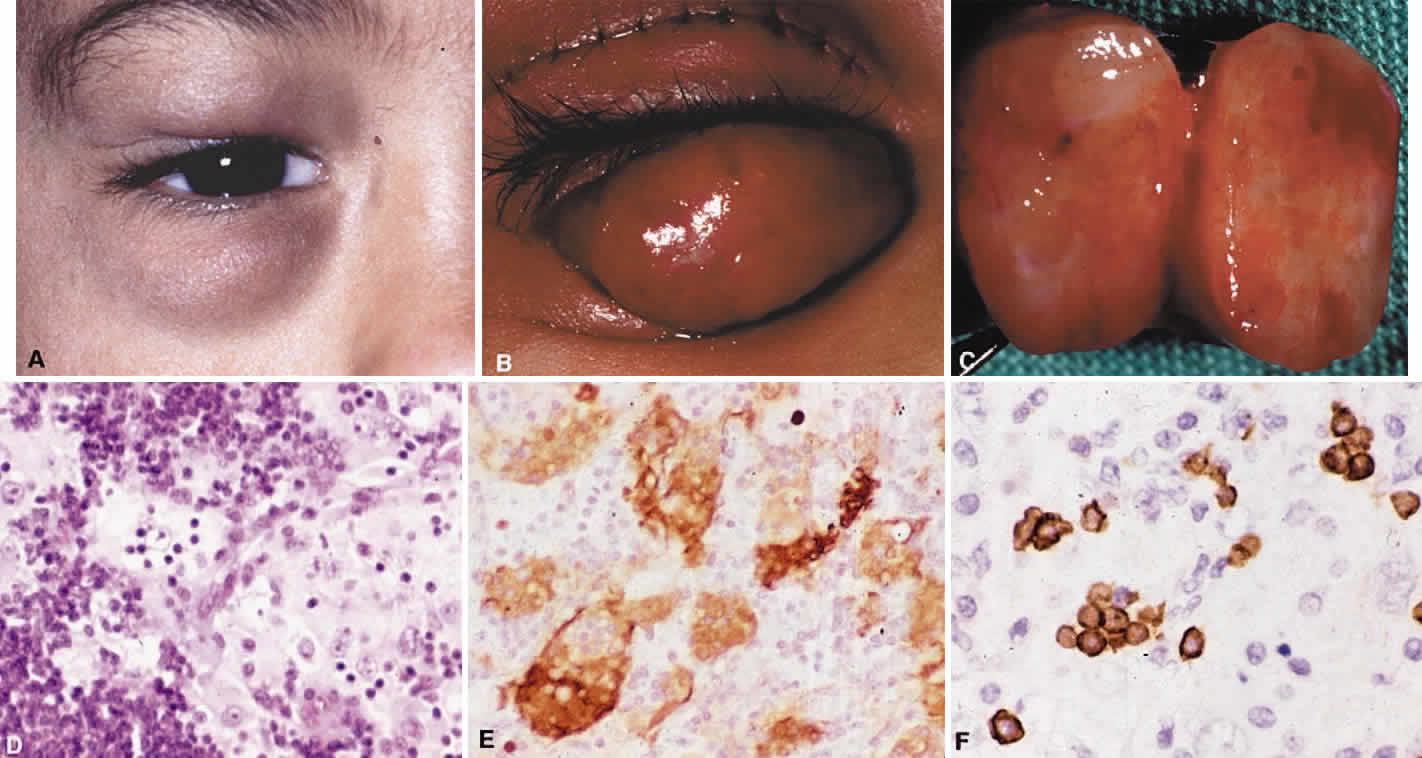

Systemic non-Hodgkin's lymphomas usually present with painless lymph node enlargement in one or more nodes. Adults usually are in their fifth or sixth decade, and presentation in childhood is extremely rare. The fever, night sweats, and weight loss characteristic of Hodgkin's disease generally are absent. Splenomegaly may develop in 20% of patients. Patients usually have normal blood counts, although they may develop lymphocytosis, especially with well-differentiated lymphocytic lymphomas, or pancytopenia with anemia, hemorrhage, petechiae, ecchymosis, and infection—the pancytopenia occurring in one third of patients as a result of bone marrow involvement or chemotherapy and radiation. Patients with B-cell lymphomas tend to develop difficulty with bacterial infection, whereas those with T-cell lymphoma may develop difficulty with delayed-type hypersensitivity and viral infections. Leukemic conversion is rare in adults, although it occurs in 25% of children. In children, an acute leukemic phase may be the initial presentation. Furthermore, children are more likely to develop extranodal and aggressive disease, although they may respond well to therapy.50 In a series of 1269 patients, of whom only 3 (0.42%) presented initially with proptosis, one third of patients presented with extranodal disease and a few with bone marrow invasion.51 There was a 1.3% incidence rate of orbital disease secondary to systemic lymphoma.